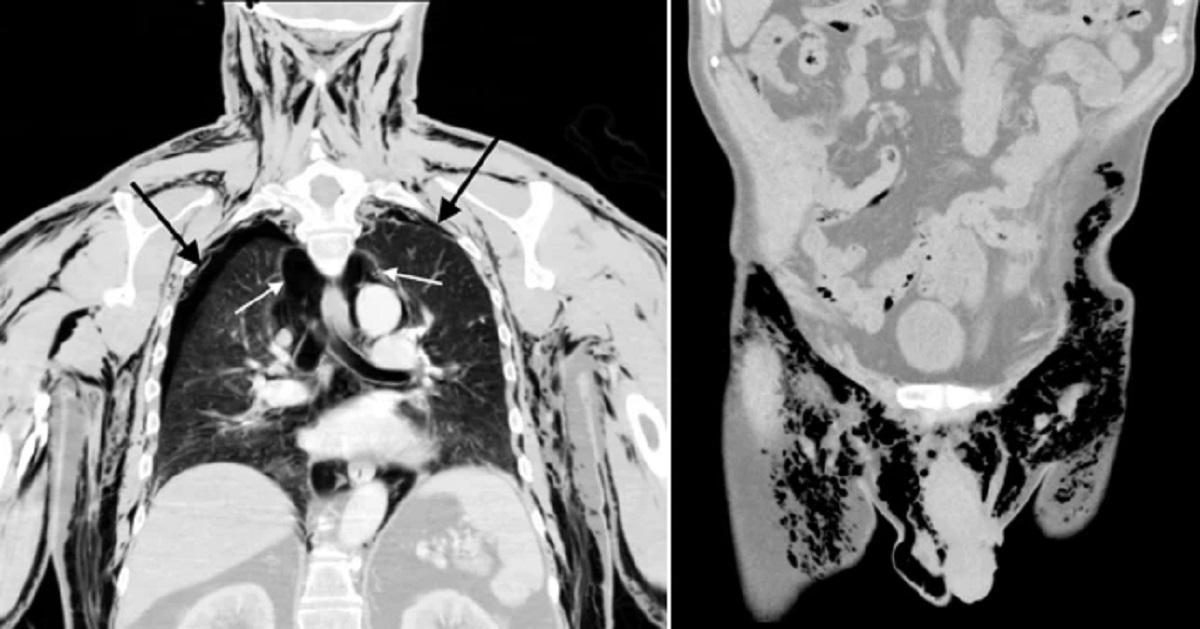

Një ekzaminim zbuloi se të moshuarit i ishin ‘shembur’ të dy mushkëritë dhe ai kishte shumë ajër që qarkullonte brenda gjoksit, gjë që ka të ngjarë të ketë qenë shkaku i ankesës së tij.

Në raport, mjekët thanë se burri ‘me vendosmëri’ mohoi të kishte injektuar ndonjë ajër në testikujt e tij që mund të kishte shkaktuar fishkëllimë. Kjo do të thotë se nuk ishte ajri i tepërt që vinte nga zona e testikujve që shkaktoi kolapsin e mushkërive të tij, por ka të ngjarë anasjelltas.

Punimi përfundoi: ‘Rasti ynë i pneumoscrotum [ fishkëllimë skotale] nga pneumotoracat dypalëshe spontane të dyshuara [mushkëritë e rrëzuara] ishte i pazakontë. Pacienti ynë kishte një plagë të hapur të skrotalit nga një procedurë e fundit e skrotalit, e cila lejoi që ajri të dilte nga pjesa e tij e barkut dhe rezultoi në shqetësimin e tij’.

Megjithatë, ai u trajtua me sukses me tuba të shumtë gjoksi, kullime ajri nënlëkuror dhe kujdes mbështetës, shkruan Metro.co.uk.